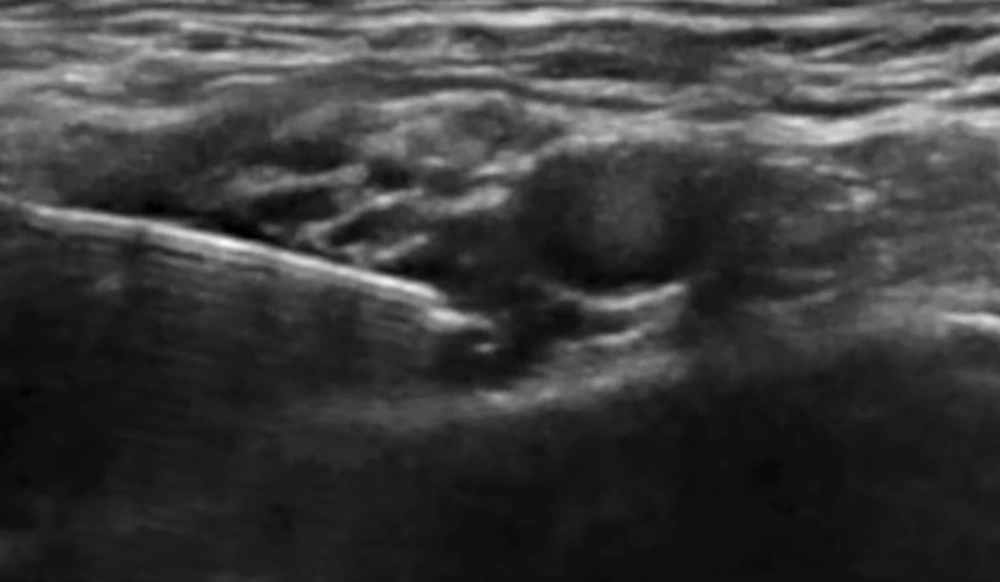

In group U, after SCPB, the ICBN was blocked under US guidance at the midaxillary level. The patient was positioned supine with the arm abducted to 90° (11). A high-frequency linear probe (6 - 12 MHz) was placed transversely over the midaxillary line at the level of the 2nd–3rd intercostal spaces. The axillary vein and artery were first visualized, then the probe was adjusted superficially to identify the fascial plane between the subcutaneous tissue and the serratus anterior muscle. The ICBN appeared as a small hyperechoic oval or linear structure within this plane. Using an in-plane, posterior-to-anterior needle approach, an 80-mm block needle was advanced into the fascial plane. After confirming negative aspiration, 5 - 8 mL of 0.25% bupivacaine was slowly injected, and real-time sonographic imaging confirmed the spread of local anesthetic along the plane both anteriorly and posteriorly (Figure 2).